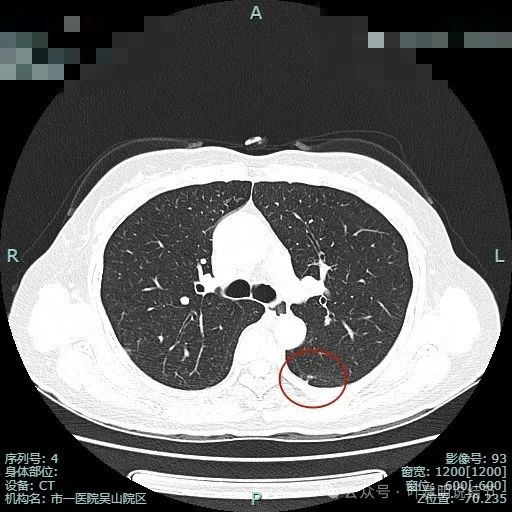

左下叶背段病灶出现(病灶1),靠叶间裂,密度不纯,若单此层当然并不一定是恶性,也可能是慢性炎的。

胸膜似略有牵拉密度不纯。